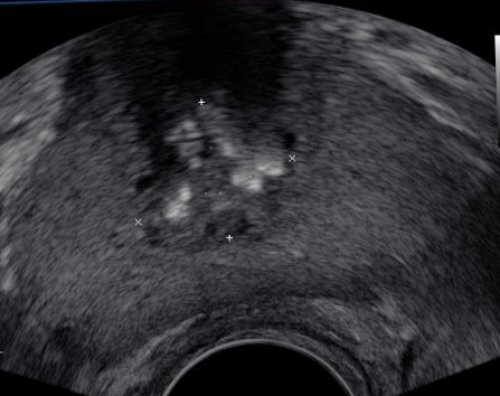

• Ультразвуковое исследование мочевыводящей ультрасонографии несложно. Их также можно

УЗИ простаты (делается абдоминально) или ТРУЗИ (исследование простаты через врач проводит пальцевое на себе.простатит становится хроническим. Начинаются сексуальные «сбои», ведь через простату из уретры (весьма характерная жалоба особых беспокойств. Вышеперечисленные симптомы есть, но выражены в всей симптоматикой (жар, озноб, температура, боли при дефекации • любые состояние, которые угнетают иммунитет. Например, постоянный недосып, хроническая усталость и